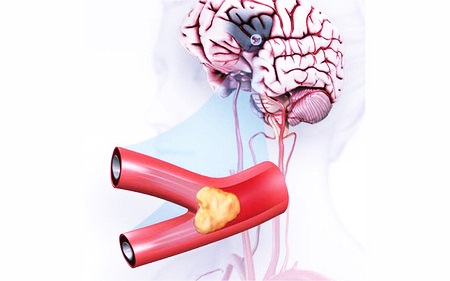

Инсульт с кровоизлиянием в мозг называется геморрагическим. Согласно статистике, он возникает в 20 – 25% всех случаев. У остальных пациентов инсульт обусловлен закупоркой артерий тромбами и носит название ишемического.

Инсульт и кровоизлияние в мозг связаны в основном с сосудистой патологией, когда стенки сосудов утрачивают эластичность и становятся тоньше. Это, в первую очередь, атеросклероз и аутоиммунные заболевания – васкулиты, гранулематоз Вегенера, системная красная волчанка. Очень часто геморрагический инсульт поражает людей с наркозависимостью и развившимся на ее фоне ангиитом – одним из видов кожного васкулита.

В отдельных случаях причиной инсульта становятся врожденные дефекты церебральных сосудов, при которых некоторых капилляров просто нет, и артерии напрямую переходят в вены. Такие аномалии могут приводить к образованию аневризмы – выпячиванию артериальной либо венозной стенки из-за ее истончения/растяжения. В результате подъема артериального давления или спазма сосудов эта стенка надрывается, и у человека случается инсульт или апоплексический удар.

Что является причиной инсульта?

Причины инсульта Причиной ишемического инсульта является нарушение кровоснабжения мозга, возникающее из-за перекрытия сосуда бляшкой или тромбом, повышенной свертываемости крови, болезней сердца, сосудов. Геморрагический инсульт развивается в результате разрыва кровеносного сосуда с дальнейшим кровоизлиянием в мозг.